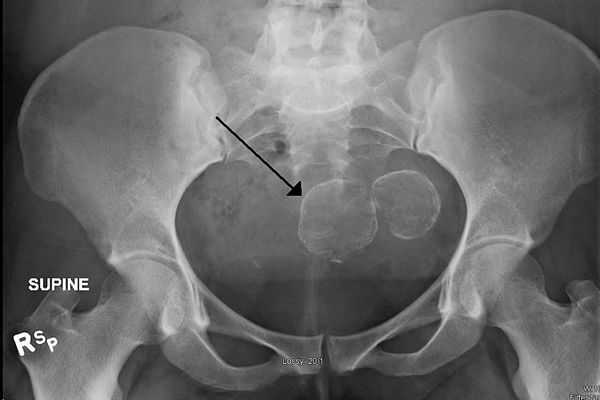

Гистеросальпингография — ценный метод для диагностики субмукозной фибромы матки. При процедуре полость матки заполняется контрастным веществом, что позволяет хорошо разглядеть на снимках выпирающие в полость матки узлы фибромы.